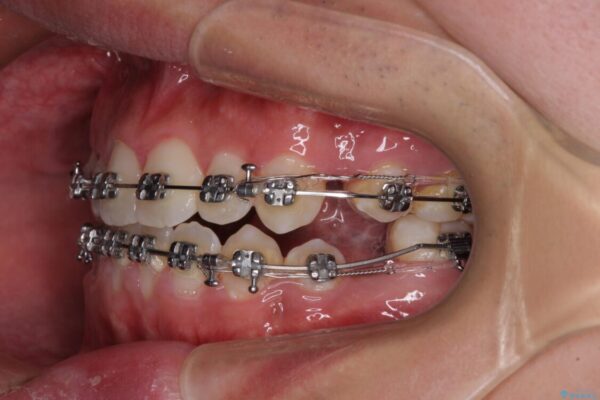

治療途中

• 口元の突出感を改善 受け口傾向の咬み合わせの抜歯矯正 治療途中画像

受け口傾向特有の狭い上顎歯列であったため、歯列の拡大を補助装置で行い、下顎歯列全体を後方に移動させることとしました。

奥歯の咬み合わせを改善させた後、上下左右の小臼歯(下顎は残存乳歯)を計4本抜歯し、ワイヤー装置にて口元の突出感を改善しながら咬み合わせを整えることとしました。

受け口傾向の方の抜歯矯正は、下顎前歯が舌側に倒れることで歯肉退縮を起こしやすいことが知られていますが、ワイヤーに工夫をすることでリスクを軽減させています。